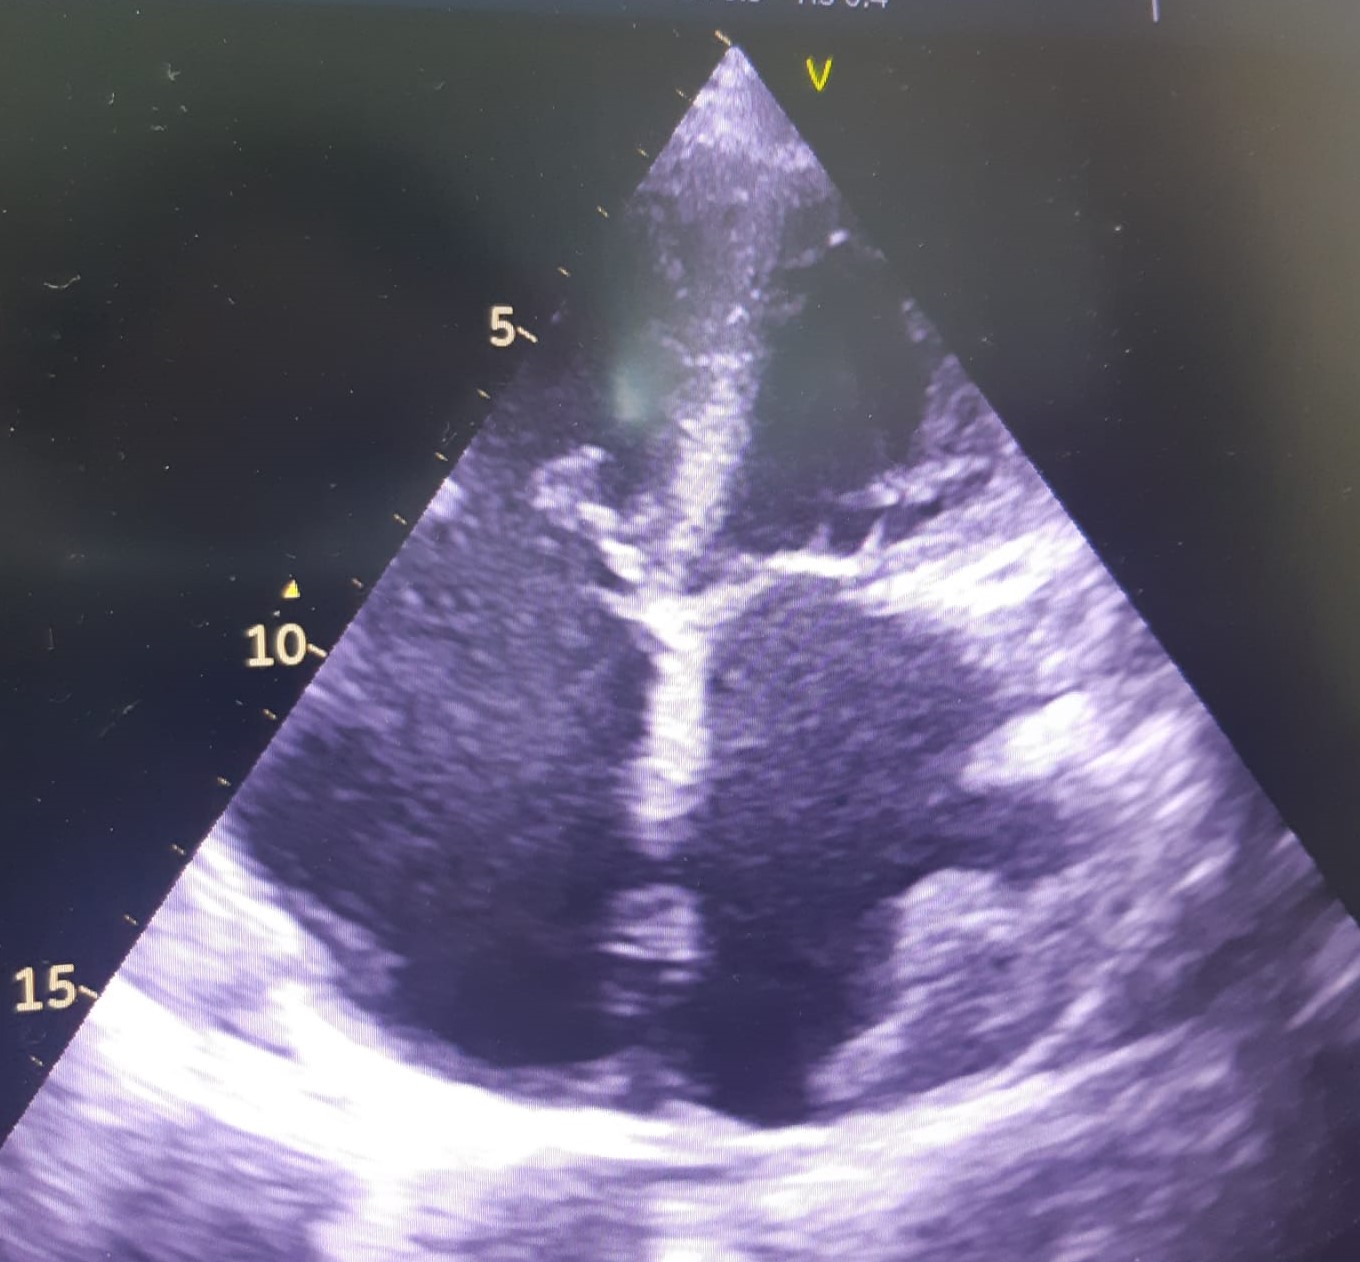

Fig. 4.Echocardiographic aspect of HCM. (A) Apical 4 chamber view systolic frame, showing increased septum thickness. (B) Apical 4 chamber view diastolic frame. (C) Parasternal long-axis view- evidence of systolic anterior motion of the mitral valve. An online video of this patient with HCM is available (Appendix Video 4).

2D echocardiography in HCM detects a septal wall thickness higher than 14 mm as

a diagnostic criterion for HCM, after excluding all the other causes of LV

hypertrophy. The severity and distribution of hypertrophy in HCM are highly

variable [23]. It may be concentric or localized (septal, apical, free LV wall,

or right ventricle hypertrophy) with or without intraventricular obstruction

(medio-ventricular, LV outflow). One pathognomonic echocardiographic feature is

the asymmetric septal hypertrophy, with a ratio of septal to the posterior wall

thickness of 1.5/1 [29]. The first echocardiographic criterion for the diagnosis

of LV hypertrophy is the LV mass obtained by M-mode and defined by an LV mass

index